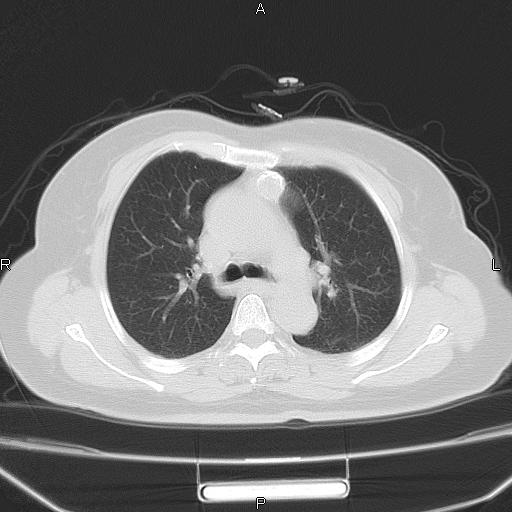

胸腺瘤

女、63Y 双眼睑下垂,早轻晚重。 胸腺瘤???

结果胸腺瘤